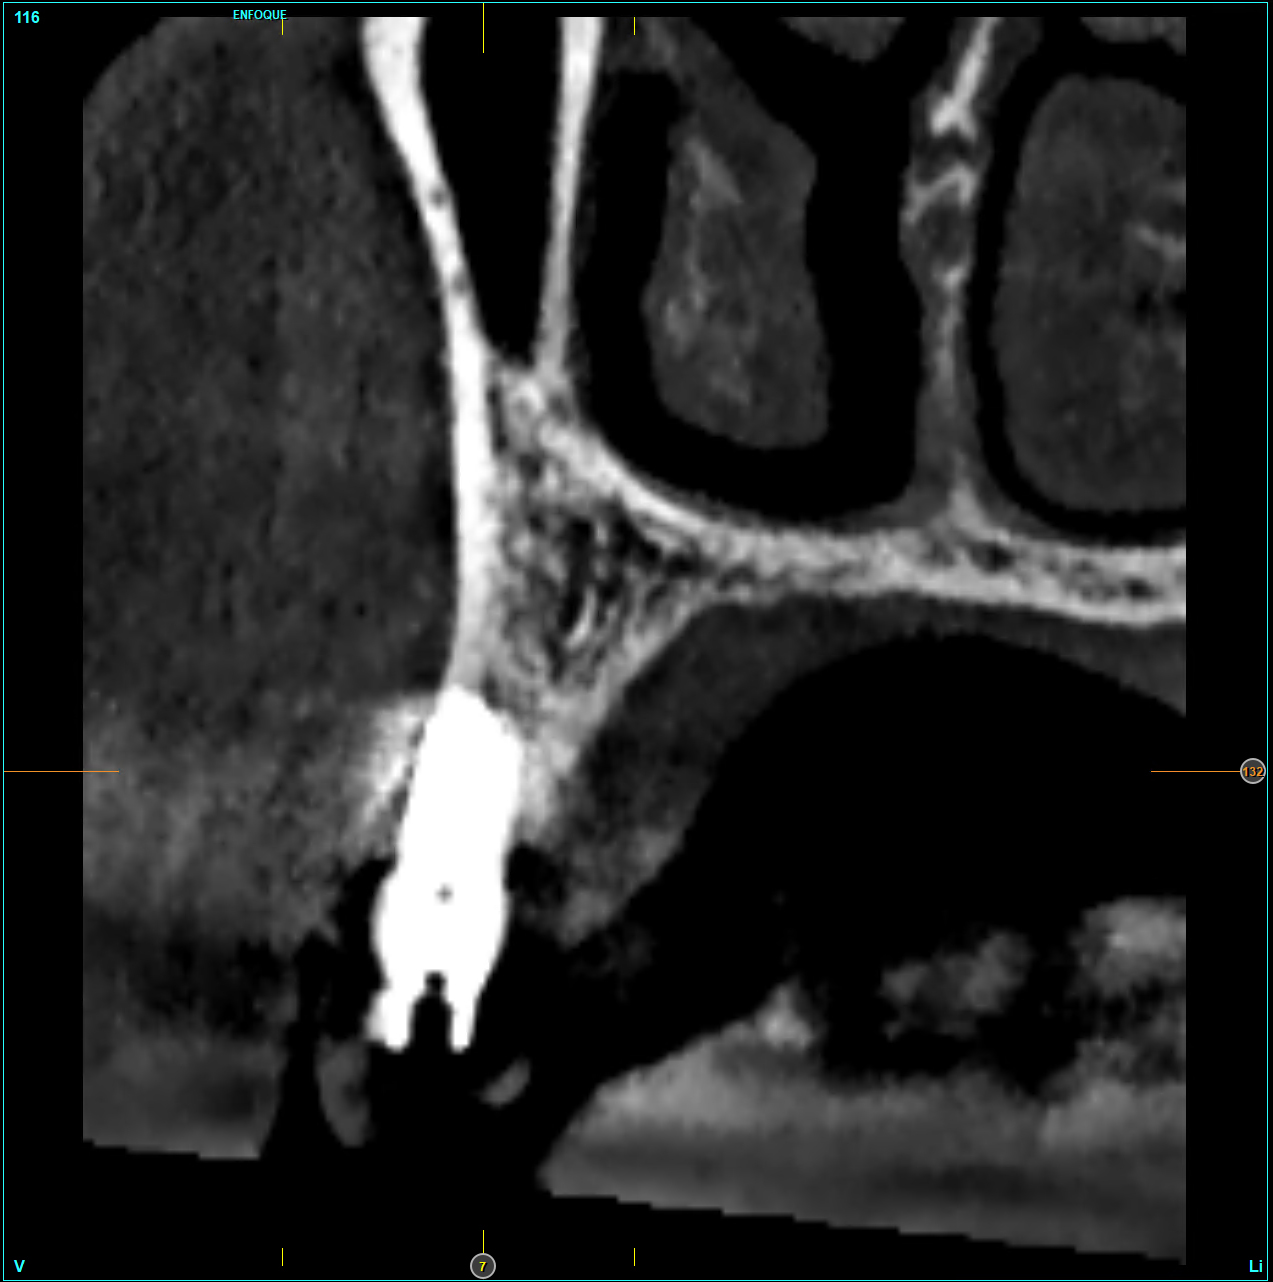

Le OPT a posizionamento del paziente standardizzato sono state eseguite alla consegna della protesi (3 mesi per la mandibola, 6 mesi per la maxilla) e a 1,3, 6 e 12 mesi dopo il carico. Le radiografie sono state calibrate con ImageJ utilizzando l’impianto di lunghezza conosciuta per correggere la magnificazione, mentre la perdita d’osso marginale è stata misurata dalla spalla dell’impianto al primo punto di contatto tra osso e impianto. Il dato principale è la perdita di osso marginale mesiale e distale; i dati secondari sono invece la sopravvivenza degli impianti e le complicazioni chirurgiche/protesiche. Il test di Shapiro-Wilk verifica la normalità; le variabili qualitative sono riassunte in base alla frequenza, mentre le variabili quantitative in base a media e deviazione standard. La sopravvivenza è analizzata con lo stimatore di Kaplan-Meier utilizzando il software SPSS v15.0 (Statistical Package for Social Science versione 15.0).

Il 20% degli impianti è stato posizionato nella mandibola (per lo più in posizione 47) e il restante 80% nel mascellare superiore (il 20% in posizione 16 e il 20% in posizione 25). Gli impianti posizionati nel mascellare superiore hanno trovato un osso tipo IV, mentre gli impianti posizionati nella mandibola hanno trovato un osso tipo III. Gli impianti utilizzati hanno un diametro compreso tra 4.0 e 4,5 mm (il 66.7% sono da 4.0 mm) e una lunghezza compresa tra 4.5 mm e 7.5 mm (il 53.3% sono lunghi 7.5 mm). Nell’86.7% dei casi non è stato eseguito alcun procedimento chirurgico aggiuntivo; in un caso, due impianti hanno previsto in rialzo di seno transcrestale con PRGF-Endoret e osso autologo. Nel 93.3% dei casi la protesizzazione ha previsto ponti avvitati a più elementi; un impianto è stato protesizzato mediante elemento singolo avvitato con componente transepiteliale. Il follow-up medio è stato di 12.4 ± 1.05 mesi dal carico. Il 100% degli impianti è sopravvissuto, senza complicanze né chirurgiche né protesiche. La perdita di osso media a 12 mesi è stata mesialmente di 0.15 ± 0.74 mm e distalmente di 0.13 ± 0.85 mm. La Figura 4 mostra l’osso perso su un singolo impianto e le Figure 5-14 illustrano un caso clinico rappresentativo.

Nel nostro studio, la sopravvivenza del 100% e la perdita di osso <0.25 mm a 12 mesi indicano una performance eccellente. La pianificazione virtuale e le guide statiche riducono errori di angolazione e profondità (approssimativamente 3.3° e <1 mm, rispettivamente) migliorando i risultati quando combinati con la densificazione ossea.